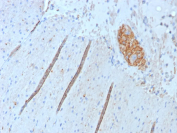

NCAM CD56 Antibody (clone NCAM1/9074R). Immunohistochemistry of FFPE human colon tissue demonstrates membranous and cytoplasmic staining in scattered neural and neuroendocrine-associated structures consistent with expression of Neural cell adhesion molecule 1 (NCAM1), also known as CD56. Brown chromogenic signal highlights NCAM1-positive cells within nerve fibers and localized cell clusters embedded in the surrounding stromal tissue, while most epithelial and stromal cells show minimal staining. Heat-induced epitope retrieval was performed by boiling tissue sections in pH 9 10mM Tris with 1mM EDTA for 20 minutes followed by cooling prior to antibody incubation.